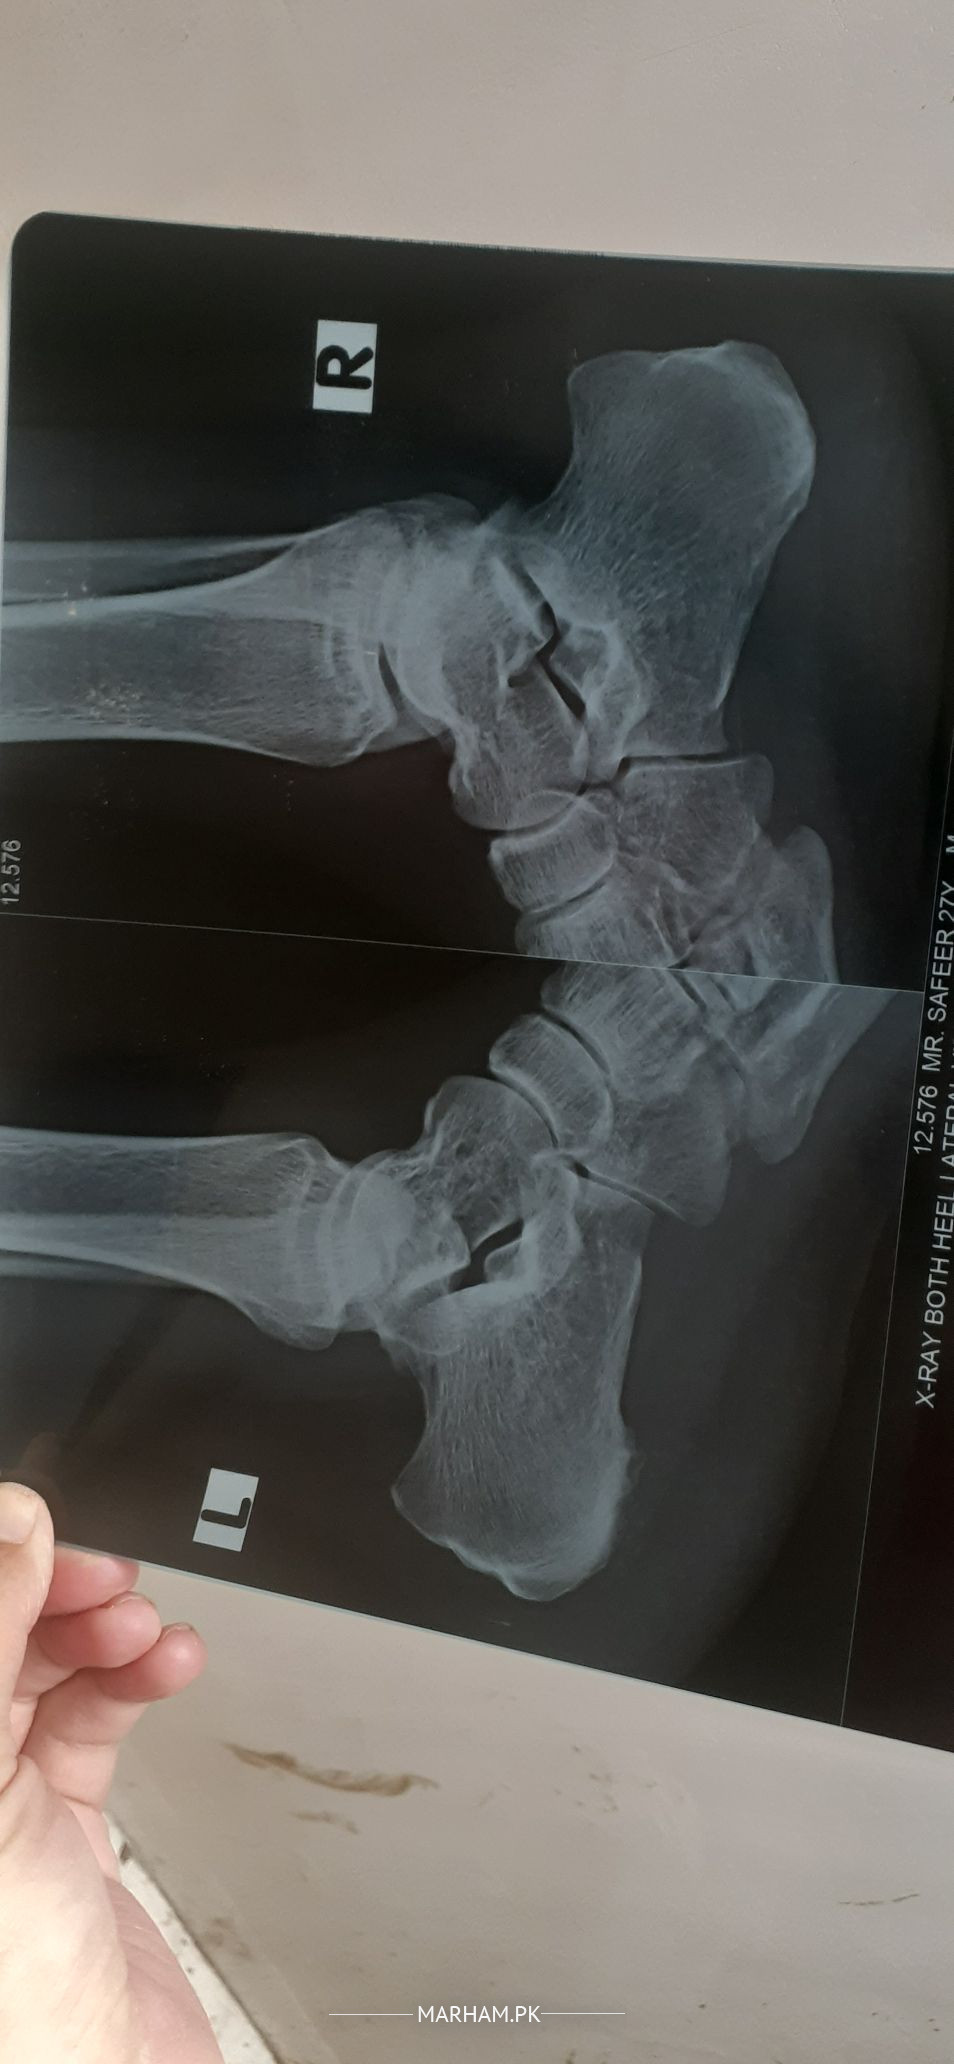

sir mery right back side pa boht zaida swelling or dard ha 1 year ho gia ha or sath left foot ki hell ha boht zaida treetment ki koi farq ni or xry share karta hon..